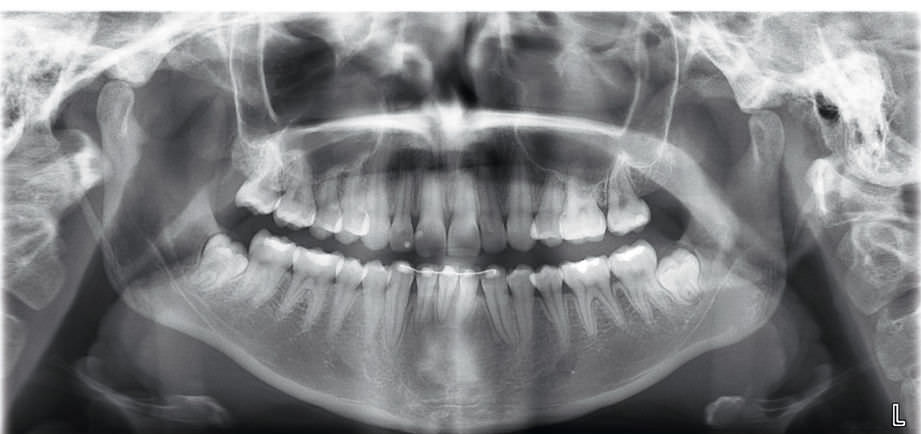

A radiografia panorâmica é um exame completo realizado no é um raio-x sobre o complexo maxilo-mandibular. Trata-se de uma das técnicas radiográficas mais solicitadas e difundidas em todas as especialidades da Odontologia, pois sua realização permite a visualização de todos os elementos dentais e suas estruturas anatômicas.

O exame é útil, prático e um dos principais auxiliares do exame clínico no diagnóstico das doenças dos dentes e dos ossos da face. De posse da radiografia panorâmica do paciente, o dentista pode visualizar todos os dentes, inclusive os que ainda não nasceram. Também é possível diagnosticar cáries, fraturas dentais, infecções ou outras doenças dos ossos que sustentam os dentes.